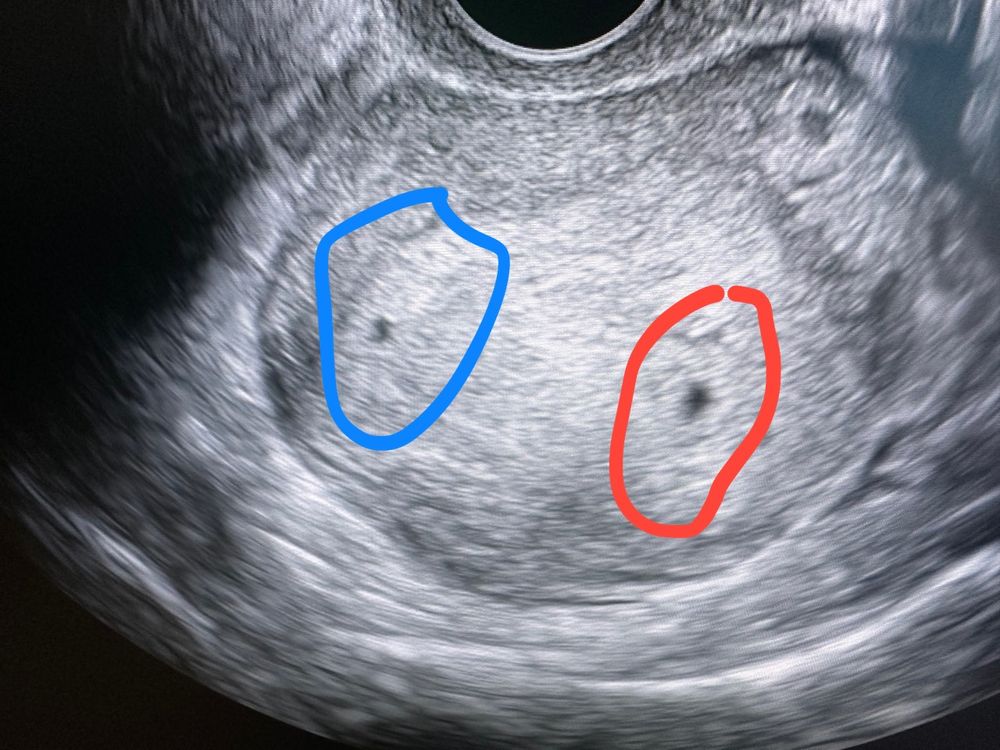

Была сейчас на узи, врач сказала, что матка большая для моего срока. В матке одно плодное яйцо нормальных размеров, второе под вопросом меньше в 2 раза. Что думаете? У кого-то было подобное? Теперь не знаю что думать

Ну либо у вас одно остановилось в развитии и редуцируется само, либо была вторая овуляция и это второй малыш:)

Смотрите в динамике:) В любом случае поздравляю, ваш малышок с вами, даже если один малыш остановился, второму это ничем не грозит.